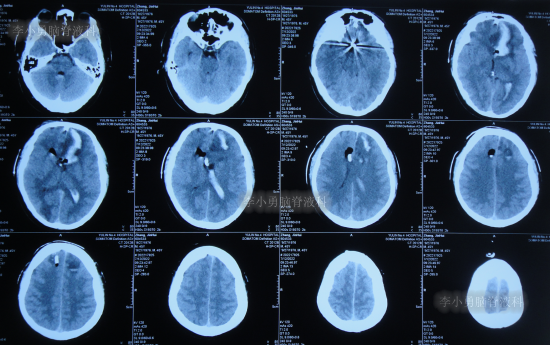

患者于2022年7月8日凌晨突发头痛,伴有胡言乱语,右下肢明显乏力,被家属送至附近的陕西省榆林市某医院,查头颅CT示脑出血(图-1),考虑脑动脉瘤破裂;当即给予了DSA检查发现前交通动脉瘤(图-2)。

图-1:2022年7月8日头颅CT

脑动脉瘤栓塞术后4天即2022年7月12日,查头颅CT示仍有积血(图-4)。

图-4:2022年7月12日头颅CT

拔除引流管后10天即2022年7月25日(脑动脉瘤栓塞术后17天),查头颅CT示脑室周水肿,仍有少量积血(图-5);仍间断发热,且脑脊液白细胞仍高,脑脊液浑浊。

图-5:2022年7月25日头颅CT

因病情未见好转,患者在该院治疗25天即2022年8月2日(脑动脉瘤栓塞术后25天),转到家乡的河北省某三甲医院继续治疗,查头颅CT示脑动脉瘤栓塞术后状态(图-6),仍间断高热,给予每日行腰椎穿刺治疗。

图-6:2022年8月2日头颅CT

该院治疗20余天时间内,虽每天进行腰穿治疗,但期间3次查头颅CT均显示脑室持续的扩张(图-7、图-8、图-9)。

图-7:2022年8月9日头颅CT

图-8:2022年8月14日头颅CT

图-9:2022年8月15日头颅CT